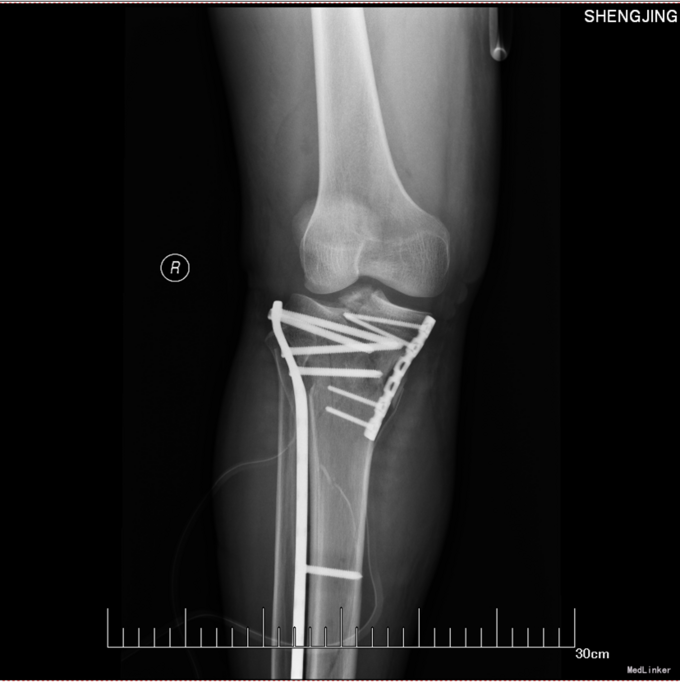

诊断:左胫骨平台骨折(SchatzkerⅣ型) 患者入院后见患肢肿胀明显,给予患肢抬高位,冷敷,甘露醇消肿等对症治疗,带患肢出现褶皱试验阳性后,全麻下行左胫骨平台骨折切口复位钢板内固定术,术后患者肿胀明显,给予抗炎,消肿,冷敷,患肢抬高等对症治疗。患者每天换药观察切口愈合情况,无红肿及渗出,待伤口14天后予以拆线治疗,予以出院,给予康复处方。